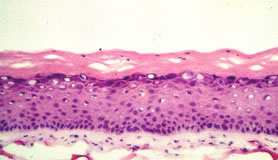

Durch sukzessives Züchten einer Dermis aus Fibroblasten und einer Epidermis mit Stratum Corneum aus Keratinocyten entsteht innerhalb von 5 Wochen ein Ganzhautmodell, das alle wesentlichen Schichten der Haut enthält (6) (Abb. 2). Die immunohistologische Analyse zeigt, dass sowohl die epidermalen Differenzierungsmarker als auch die Proteine der Basalmembran und der dermalen Matrix ähnlich exprimiert werden (Tab. 1).

Abb. 2: Histologischer Vergleich zwischen Ganzhautmodell (oben) und normaler menschlicher Haut (unten)